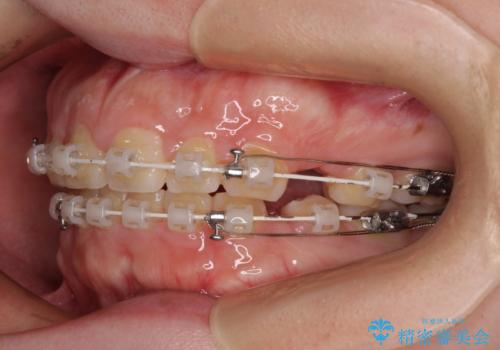

- 矯正装置

- 審美装置

- 出っ歯と口の閉じにくさ、デコボコを気にして来院された患者様です。

口元の突出感を改善するため、上下左右第一小臼歯4本の抜歯を行い、ワイヤー装置による矯正治療を行うこととしました。

抜歯矯正を行ったことで、顎先のつっぱり感や口元の閉じにくさを解消することができました。